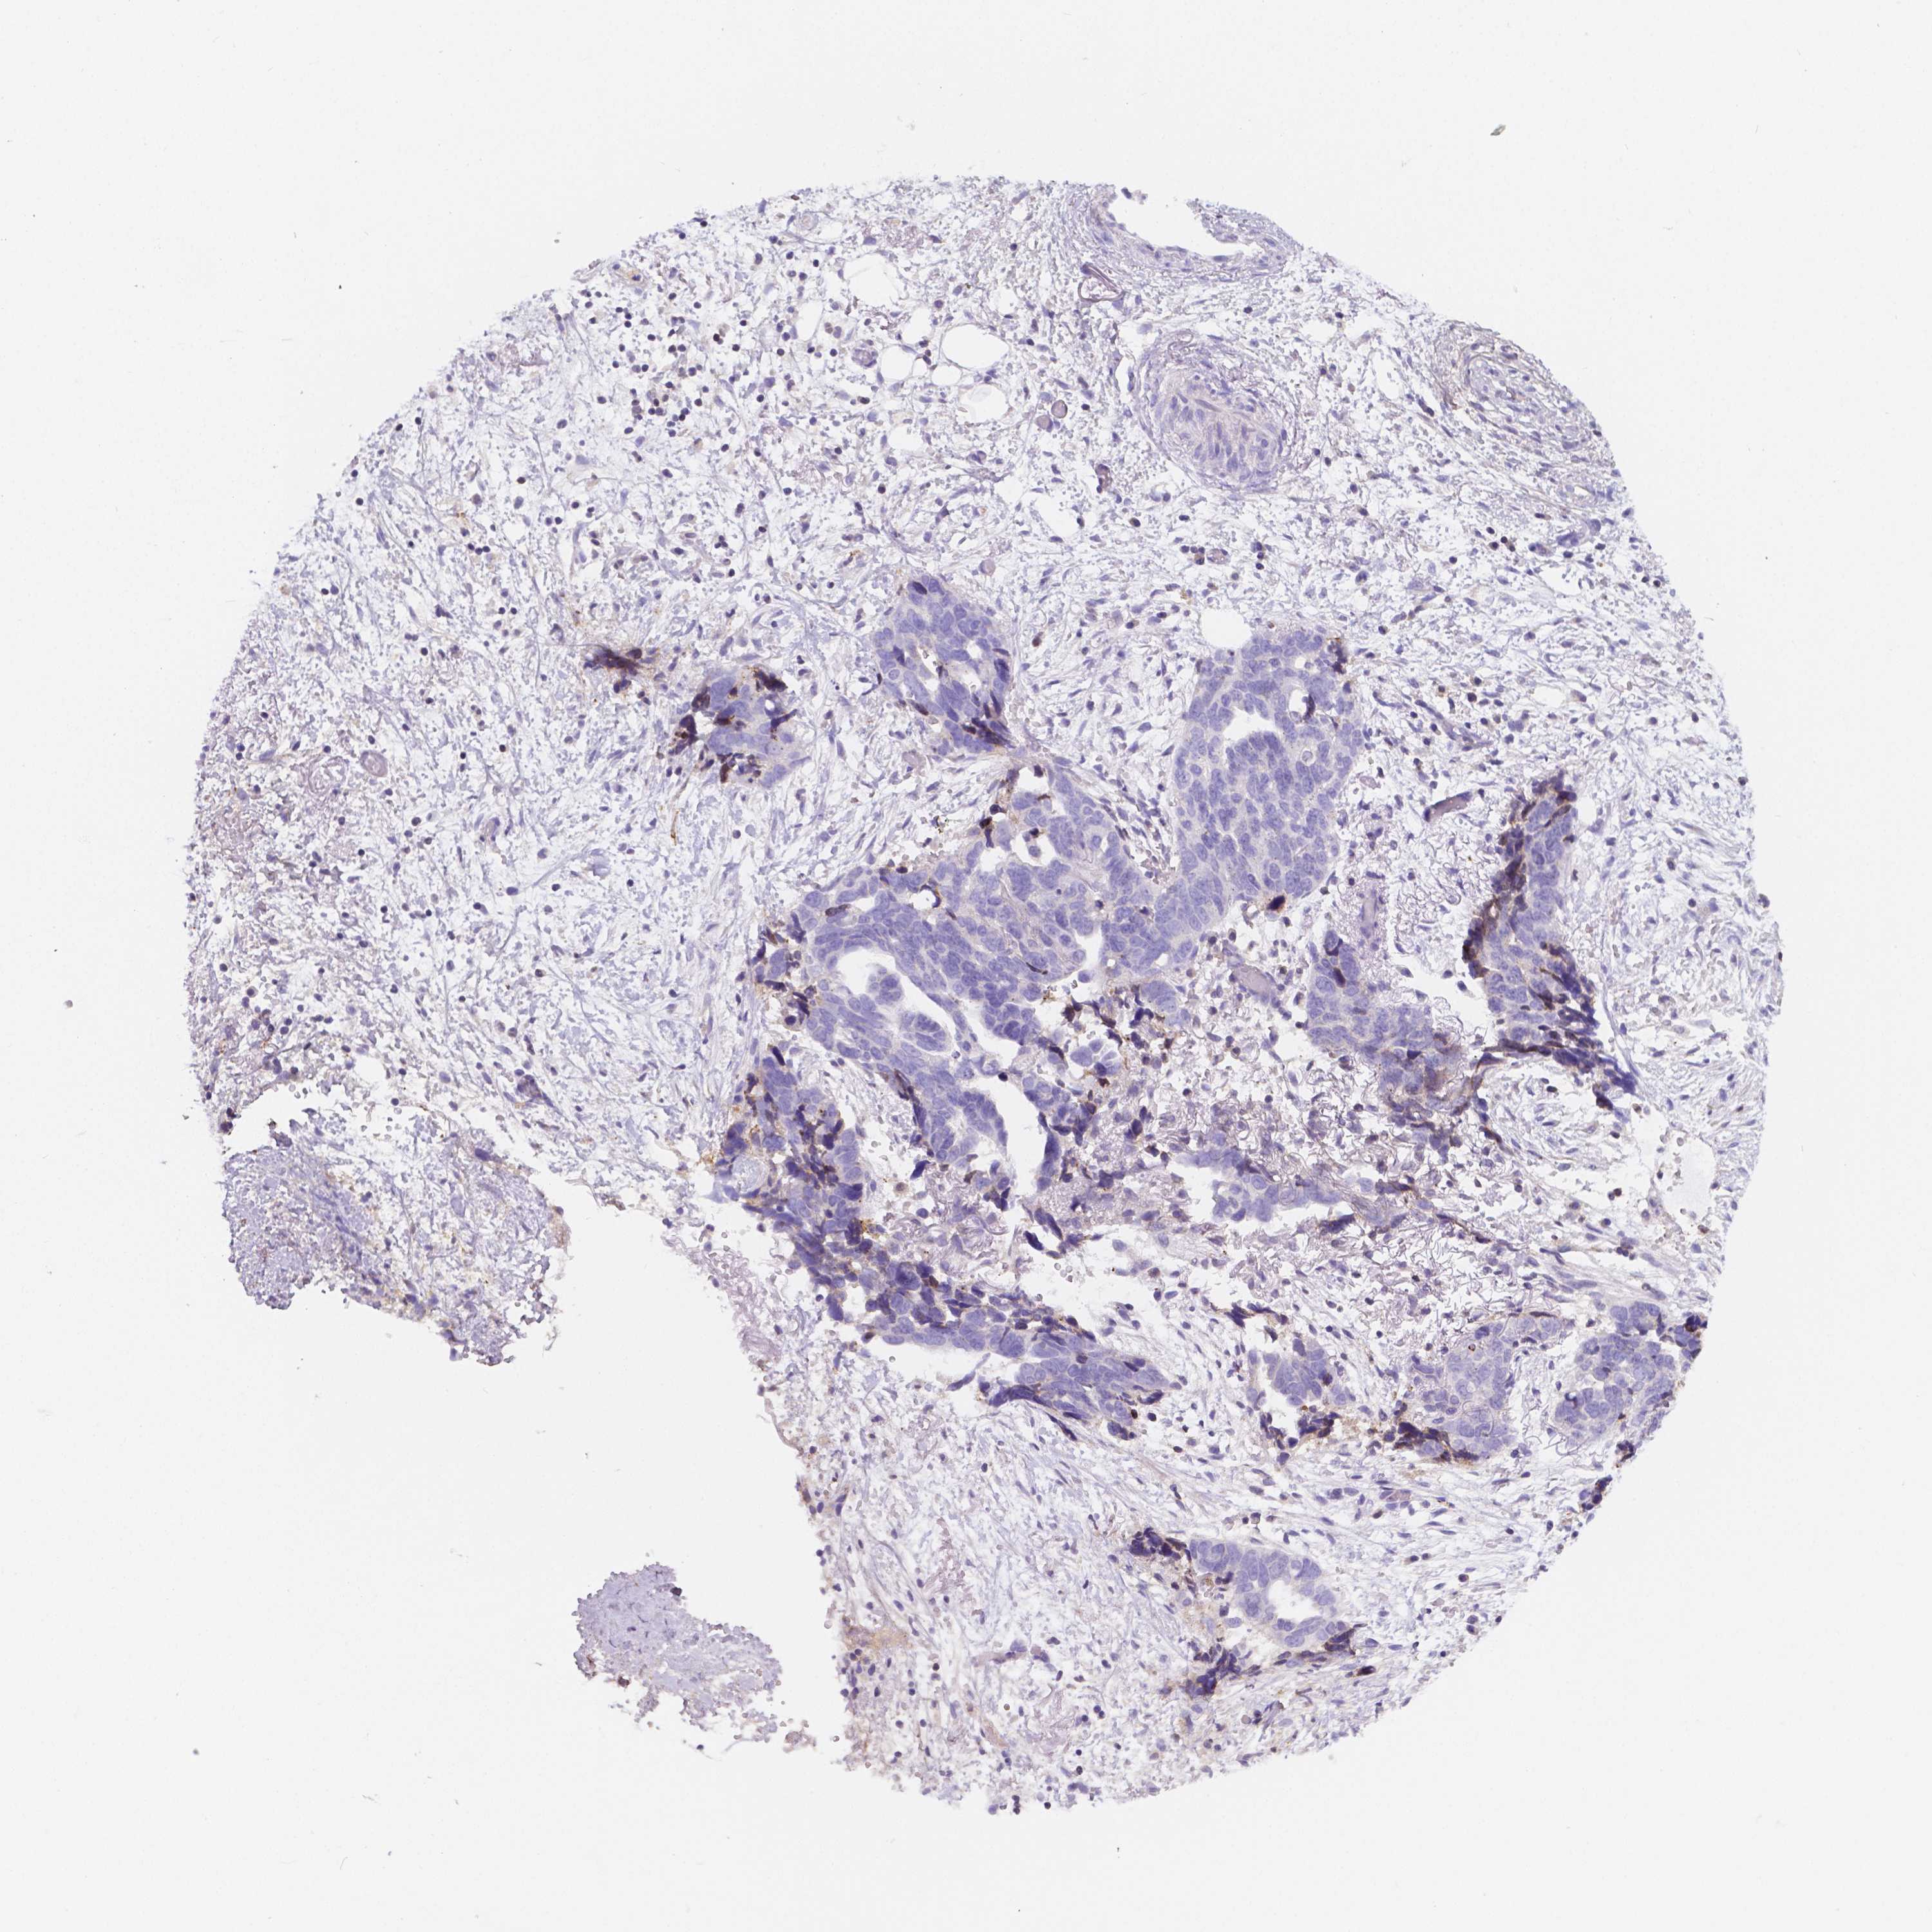

OVARIAN CANCER - Protein expressioni

A mouse-over function shows sample information and annotation data. Click on an image to view it in a full screen mode. Samples can be filtered based on level of antibody staining by selecting one or several of the following categories: high, medium, low and not detected. The assay and annotation is described here.

Note that samples used for immunohistochemistry by the Human Protein Atlas do not correspond to samples in the TCGA dataset.

Antibody stainingi

Antibody staining in the annotated cell types in the current human tissue is reported as not detected, low, medium, or high, based on conventional immunohistochemistry profiling in selected tissues. This score is based on the combination of the staining intensity and fraction of stained cells.

Each image is clickable and will lead to virtual microscopy that enables deeper exploration of all samples and also displays staining intensity scores, fraction scores and subcellular localization as well as patient and tissue information for each sample.

Antibody HPA044371

Staining

High

Medium

Low

Not detected

Intensity

Strong

Moderate

Weak

Negative

Quantity

>75%

75%-25%

<25%

None

Location

Nuclear

Cytoplasmic/membranous

Cytoplasmic/membranous,nuclear

Cystadenocarcinoma, serous, NOS

Cystadenocarcinoma, mucinous, NOS

Carcinoma, endometroid